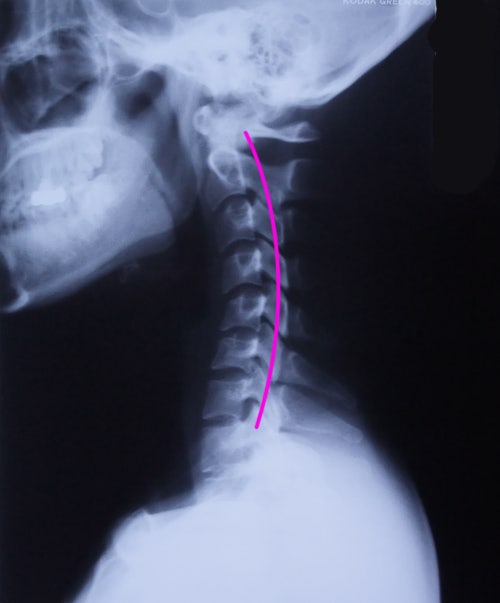

일자목 경추베개 유목민 생활 마감 (ft.찐조언)

일자목 경추베개 얼마 전에 아무 생각없이 그냥 평범한 일반 배개로 새로 바꾸고 나서 목이랑 어깨가 뻐근...